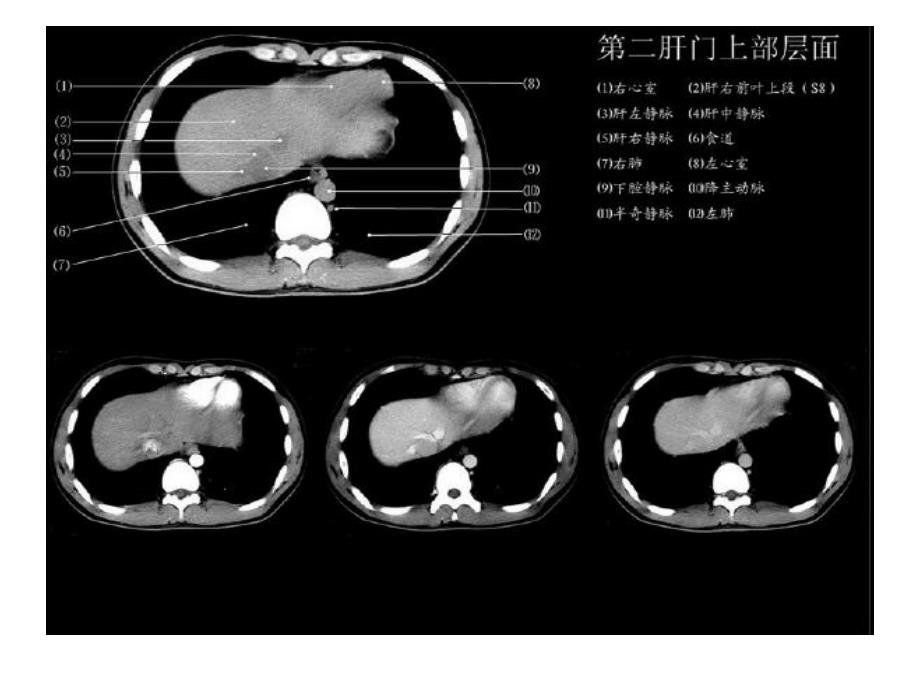

正常肝脏正常肝脏CT解剖解剖